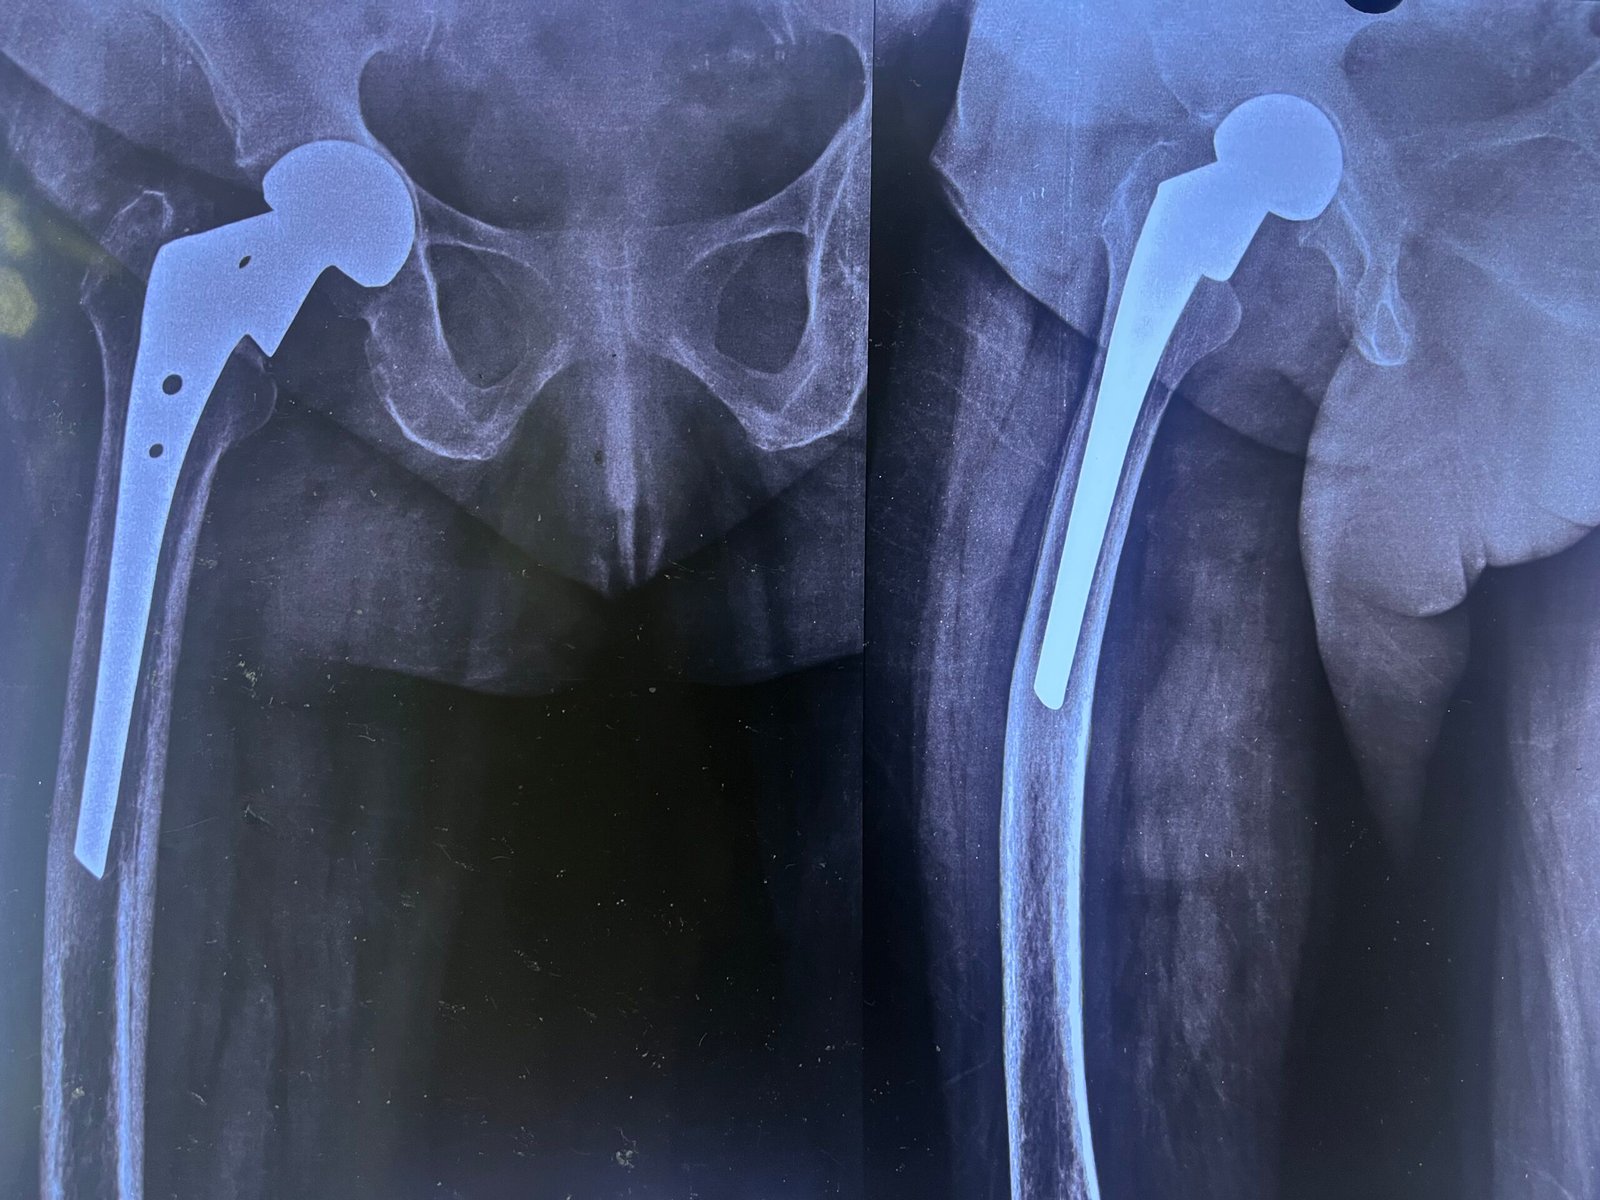

Pre-Op X-Ray

Post-Op X-Ray